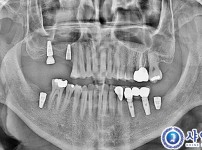

312

상악동거상술 임플란트 10개 - UV자외선